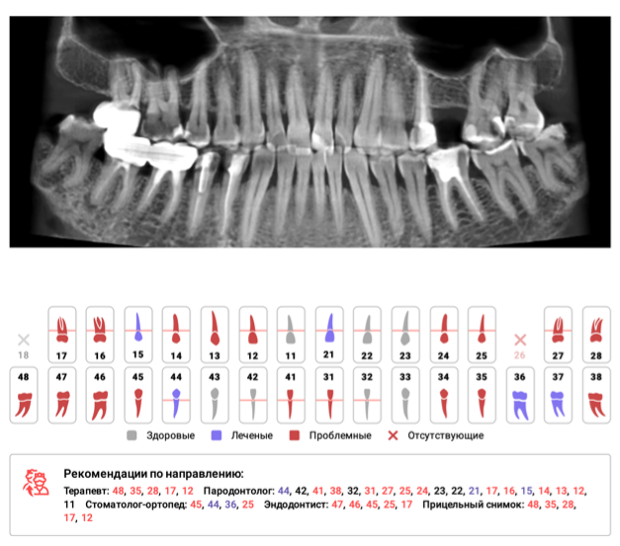

Искусственный интеллект Diagnocat — это инновационная система, которая позволяет проводить более точную и эффективную диагностику стоматологический заболеваний благодаря анализу данных с высокой точностью на основании рентгенологических снимков. Мы загружаем снимок в Diagnocat, искусственный интеллект всего за несколько минут анализирует снимок полностью, выявляет проблемы, дает отчет по каждому зубу. Доктор ставит точный диагноз. А вы сразу получаете второе независимое мнение от искусственного интеллекта.

Diagnocat способен распознавать и предсказывать возможные заболевания зубов и десен на ранних стадиях развития, что позволяет своевременно принимать необходимые меры для их предотвращения и лечения. Благодаря применению искусственного интеллекта, мы обеспечиваем нашим пациентам быструю и надежную диагностику, а также индивидуальный подход к каждому случаю.

Diagnocat помогает нашим специалистам проводить более детальное и информативное исследование состояния полости рта в рамках диагностики в процессе консультации пациентов, что в свою очередь позволяет разрабатывать оптимальные планы лечения и предотвращения заболеваний. Мы гордимся возможностью предложить нашим пациентам передовые технологии в области стоматологии, чтобы обеспечить им качественное и инновационное лечение.